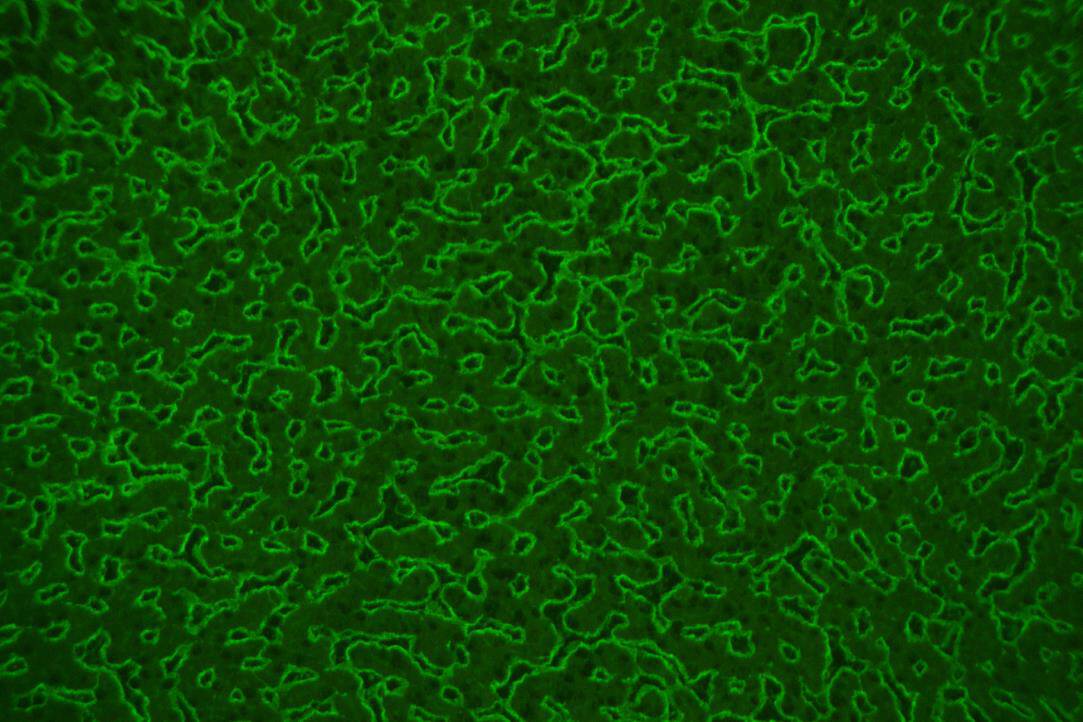

Anti-Endomysium Antibodies-ML (AEA-ML)

Monkey liver